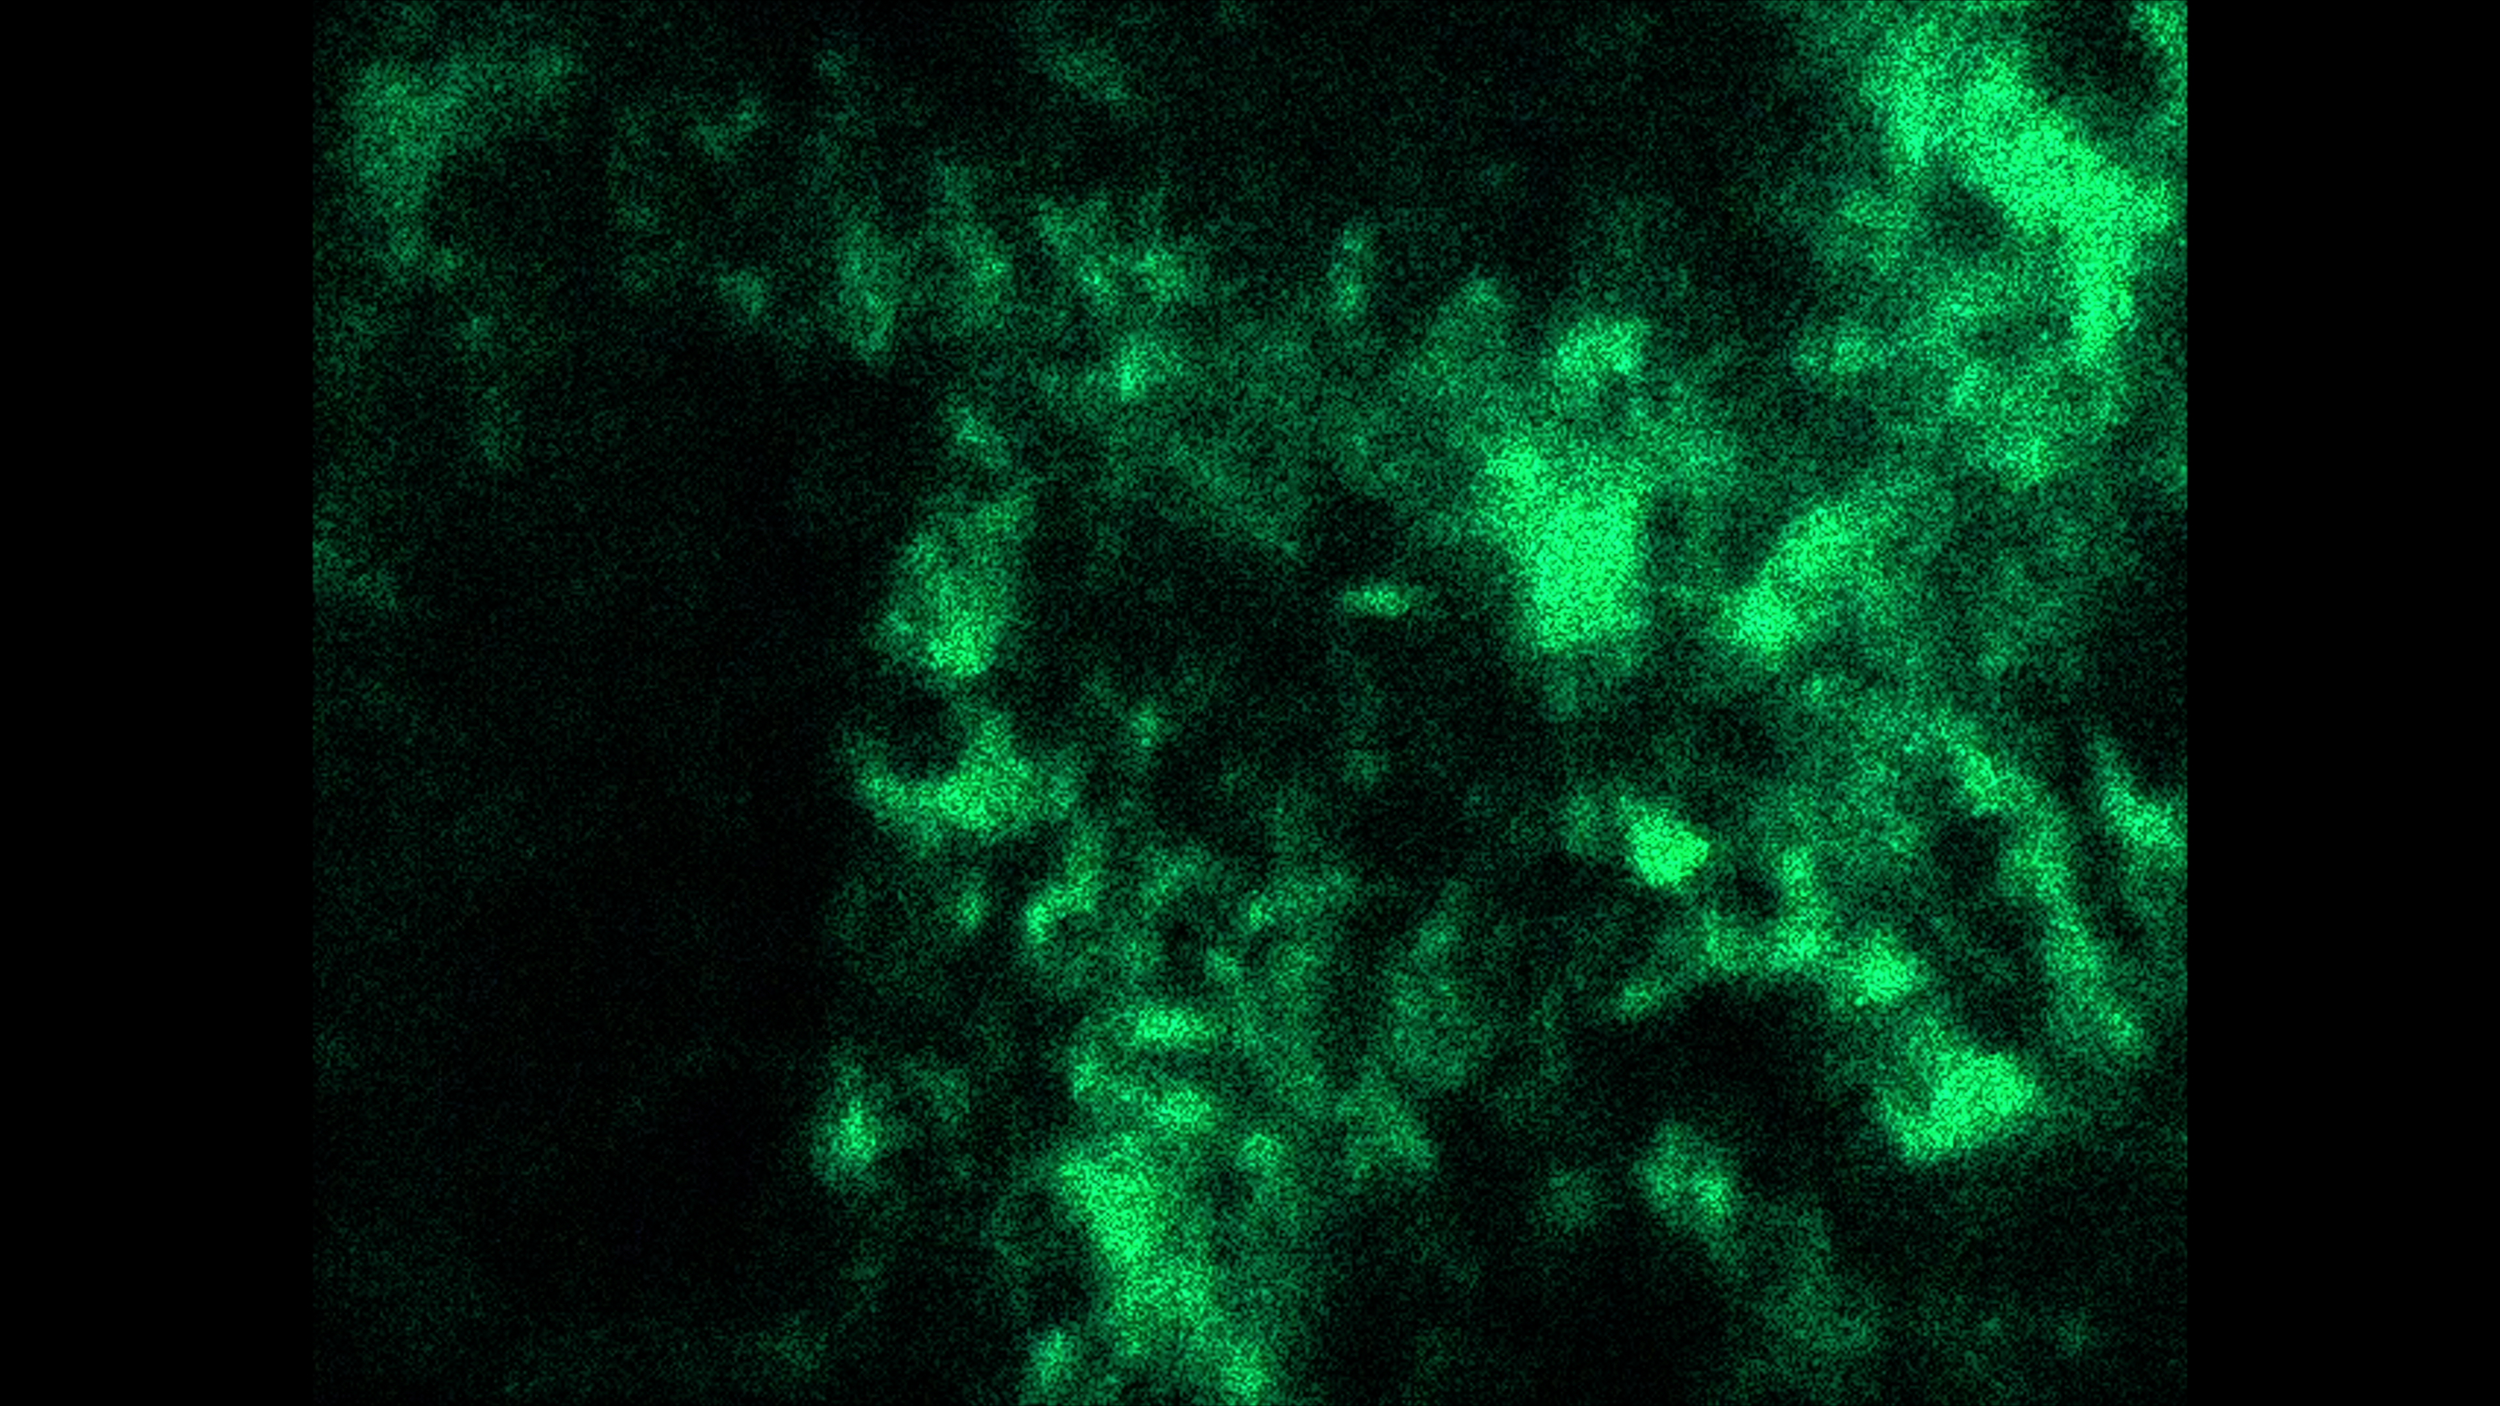

UMRDGM

View Video